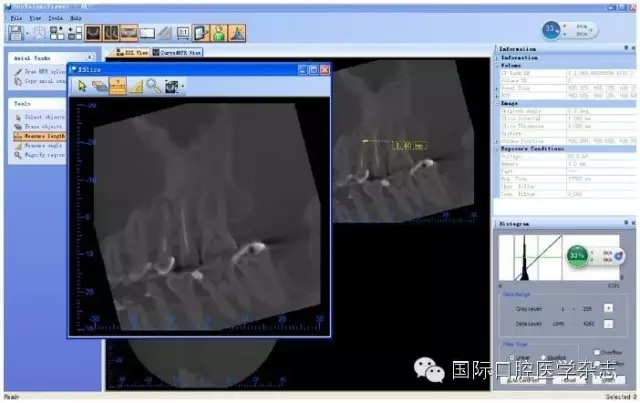

目前,對于分離器械周圍牙本質(zhì)厚度的評估以及取出后殘余牙本質(zhì)厚度的預(yù)測主要需借助影像學(xué)檢查,例如根尖片、錐形束CT(cone beamcomputed tomography,CBCT)圖像等。傳統(tǒng)的平行投照的根尖片無法反映三維立體結(jié)構(gòu),且往往存在解剖結(jié)構(gòu)影像的重疊,不利于臨床判斷,具有一定的局限性。多位學(xué)者[10]的研究表明:平行投照的根尖片會(huì)高估實(shí)際的牙本質(zhì)壁的厚度。一些學(xué)者[11-12]的研究表明:當(dāng)分離器械位于上頜第一磨牙近中根管時(shí),采用成角投照(21°)的拍攝技術(shù)與平行投照技術(shù)得到的X線片相比,能更準(zhǔn)確地評估牙本質(zhì)的厚度,為分離器械取出與否提供指導(dǎo)(圖4)。近年來,CBCT在牙髓病學(xué)中的應(yīng)用越來越廣泛,由于CBCT能清楚地反映牙及牙根周圍組織的三維立體結(jié)構(gòu),為牙本質(zhì)厚度的評估與預(yù)測提供了可行性(圖5);因此,CBCT在器械分離的病例術(shù)前風(fēng)險(xiǎn)評估方面具有較好的應(yīng)用前景。

圖 5 使用CBCT評估分離器械周圍牙本質(zhì)厚度